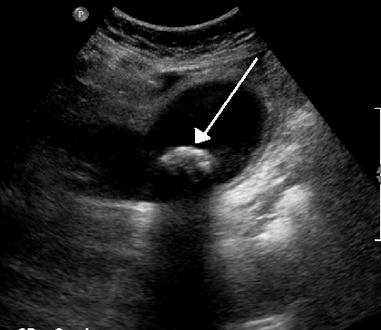

في الموجات فوق الصوتية على البطن، عادةً ما يكون لحصوات المرارة الغارقة ظل صوتي خلفي. في حصوات المرارة العائمة، يُشاهد صدى الصدى (أو قطعة أثرية على شكل ذيل المذنب) بدلاً من ذلك في حالة سريرية تسمى الورم العضلي الغدي تكون هناك علامة أخرى هي ثالوث جدار الصدى والظل (WES) (أو الظل المزدوج القوس) والذي يعد أيضًا من سمات حصوات المرارة.[37]

حصوة حجمها 1.9 سم في عنق المرارة وتؤدي إلى التهاب المرارة كما يظهر في الموجات فوق الصوتية. هناك سماكة في جدار المرارة بمقدار 4 ملم.

الحمأة الصفراوية وحصوات المرارة. هناك سماكة حدودية لجدار المرارة.